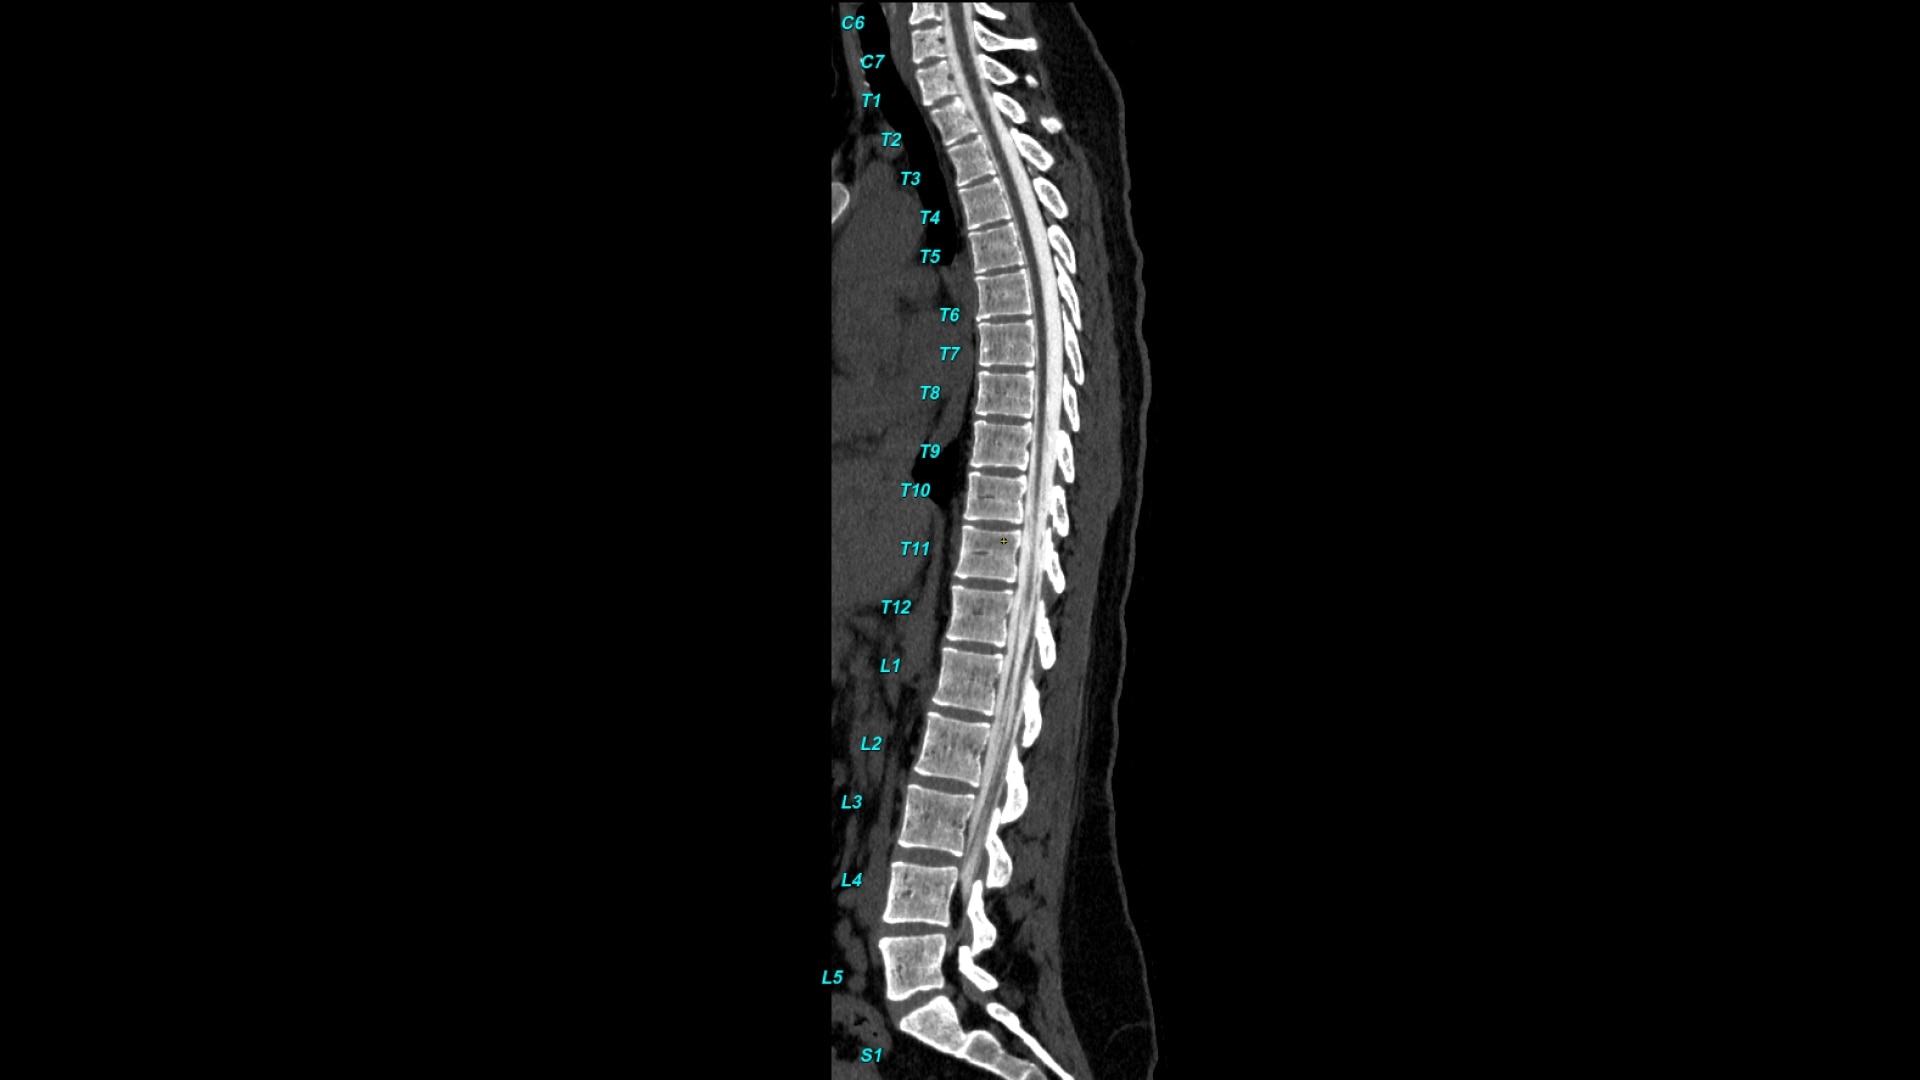

Bone VCAR

Spine assessment with deep-learning based CT application.

Automated spine identification and labelling.

>90% labeling accuracy based on Deep learning algorithm trained on global datasets acquired with a broad range of acquisition parameters.

• Automated spine labeling

• Automated generation of a 3D trace to generate oblique and straightened reformat views

• Works on full spine acquisitions as well as limited acquisitions containing segments of the spine